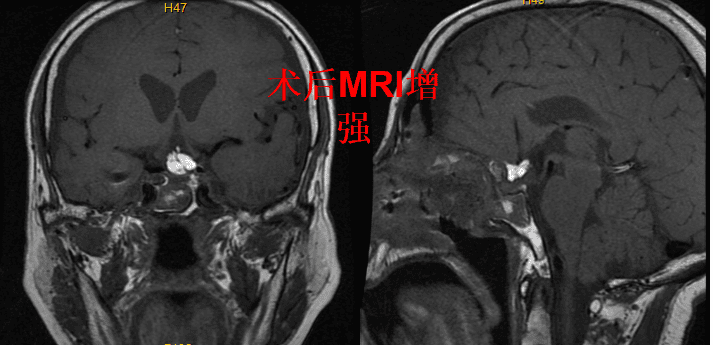

术后MRI增强可见肿瘤全切,脑积水解除

颅咽管瘤的治疗,一直是神经外科领域具有挑战性手术。颅咽管瘤位于鞍区,解剖结构复杂,毗邻众多重要神经血管,如视神经、视交叉、下丘脑、垂体及垂体柄、动眼神经,颈内动脉及其分支,大脑后动脉及其分支。颅咽管瘤的手术入路有很多种如:经额下入路、经翼点入路、经纵裂胼胝体穹隆三脑室入路开颅切除术与经鼻碟内镜下切除术。开颅手术入路需抬起脑组织,分开神经血管方能显露肿瘤,从前方或者侧方入路多由神经血管的遮挡,存在视野盲区,而经鼻扩大入路则是沿着肿瘤生长长轴显露肿瘤,可以清晰的显示肿瘤的起源,沿着与周围神经血管的边界分离肿瘤,对重要结构尤其是下丘脑的保护具有巨大优势。与开颅手术相比,经鼻手术不仅创伤小,全切率高,且术后的并发症明显减少,恢复更快。传统开手术术后患者容易出现下丘脑功能、垂体功能紊乱,需要长时间服药,远期还容易出现脑积水等并发症等。本例使用内镜经鼻碟切除鞍区颅咽管瘤,同时解除梗阻性脑积水,“一箭双雕”,具有手术时间短,术后反应轻,并发症少,对垂体功能及下丘脑功能影响小等特点。